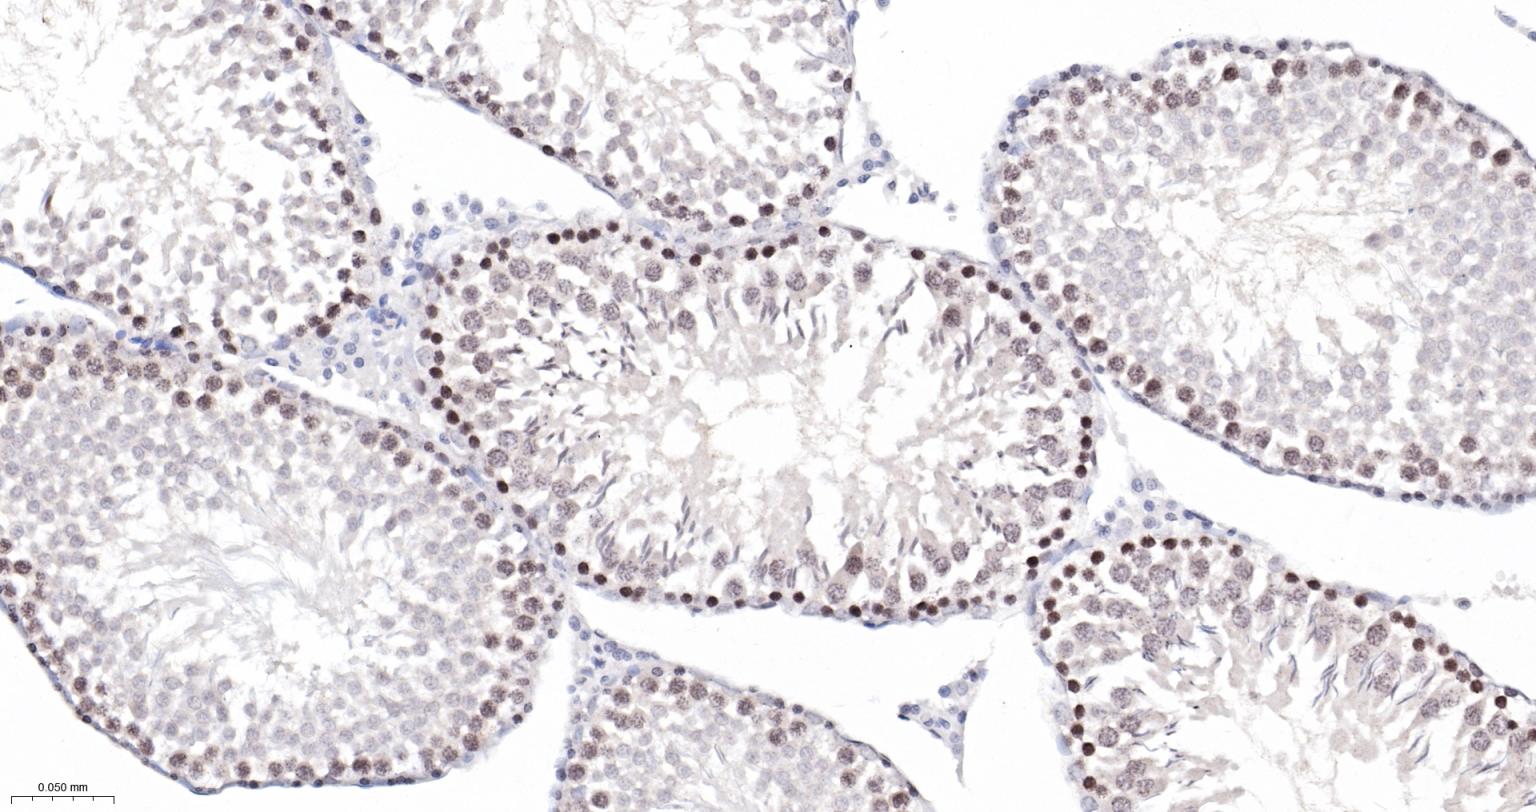

Paraformaldehyde-fixed, paraffin embedded Rat Testicles; Antigen retrieval by boiling in sodium citrate buffer (pH6.0) for 15 min; The section was incubated with Survivin Monoclonal Antibody, Unconjugated (bsm-54474R) at 1:200 overnight at 4°C, followed by conjugation to the bs-0295G-HRP and DAB (C-0010) staining.